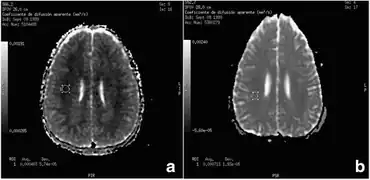

MRI -a) After 72 hours b) and after 8 months for ADC (apparent diffusion coefficient) value